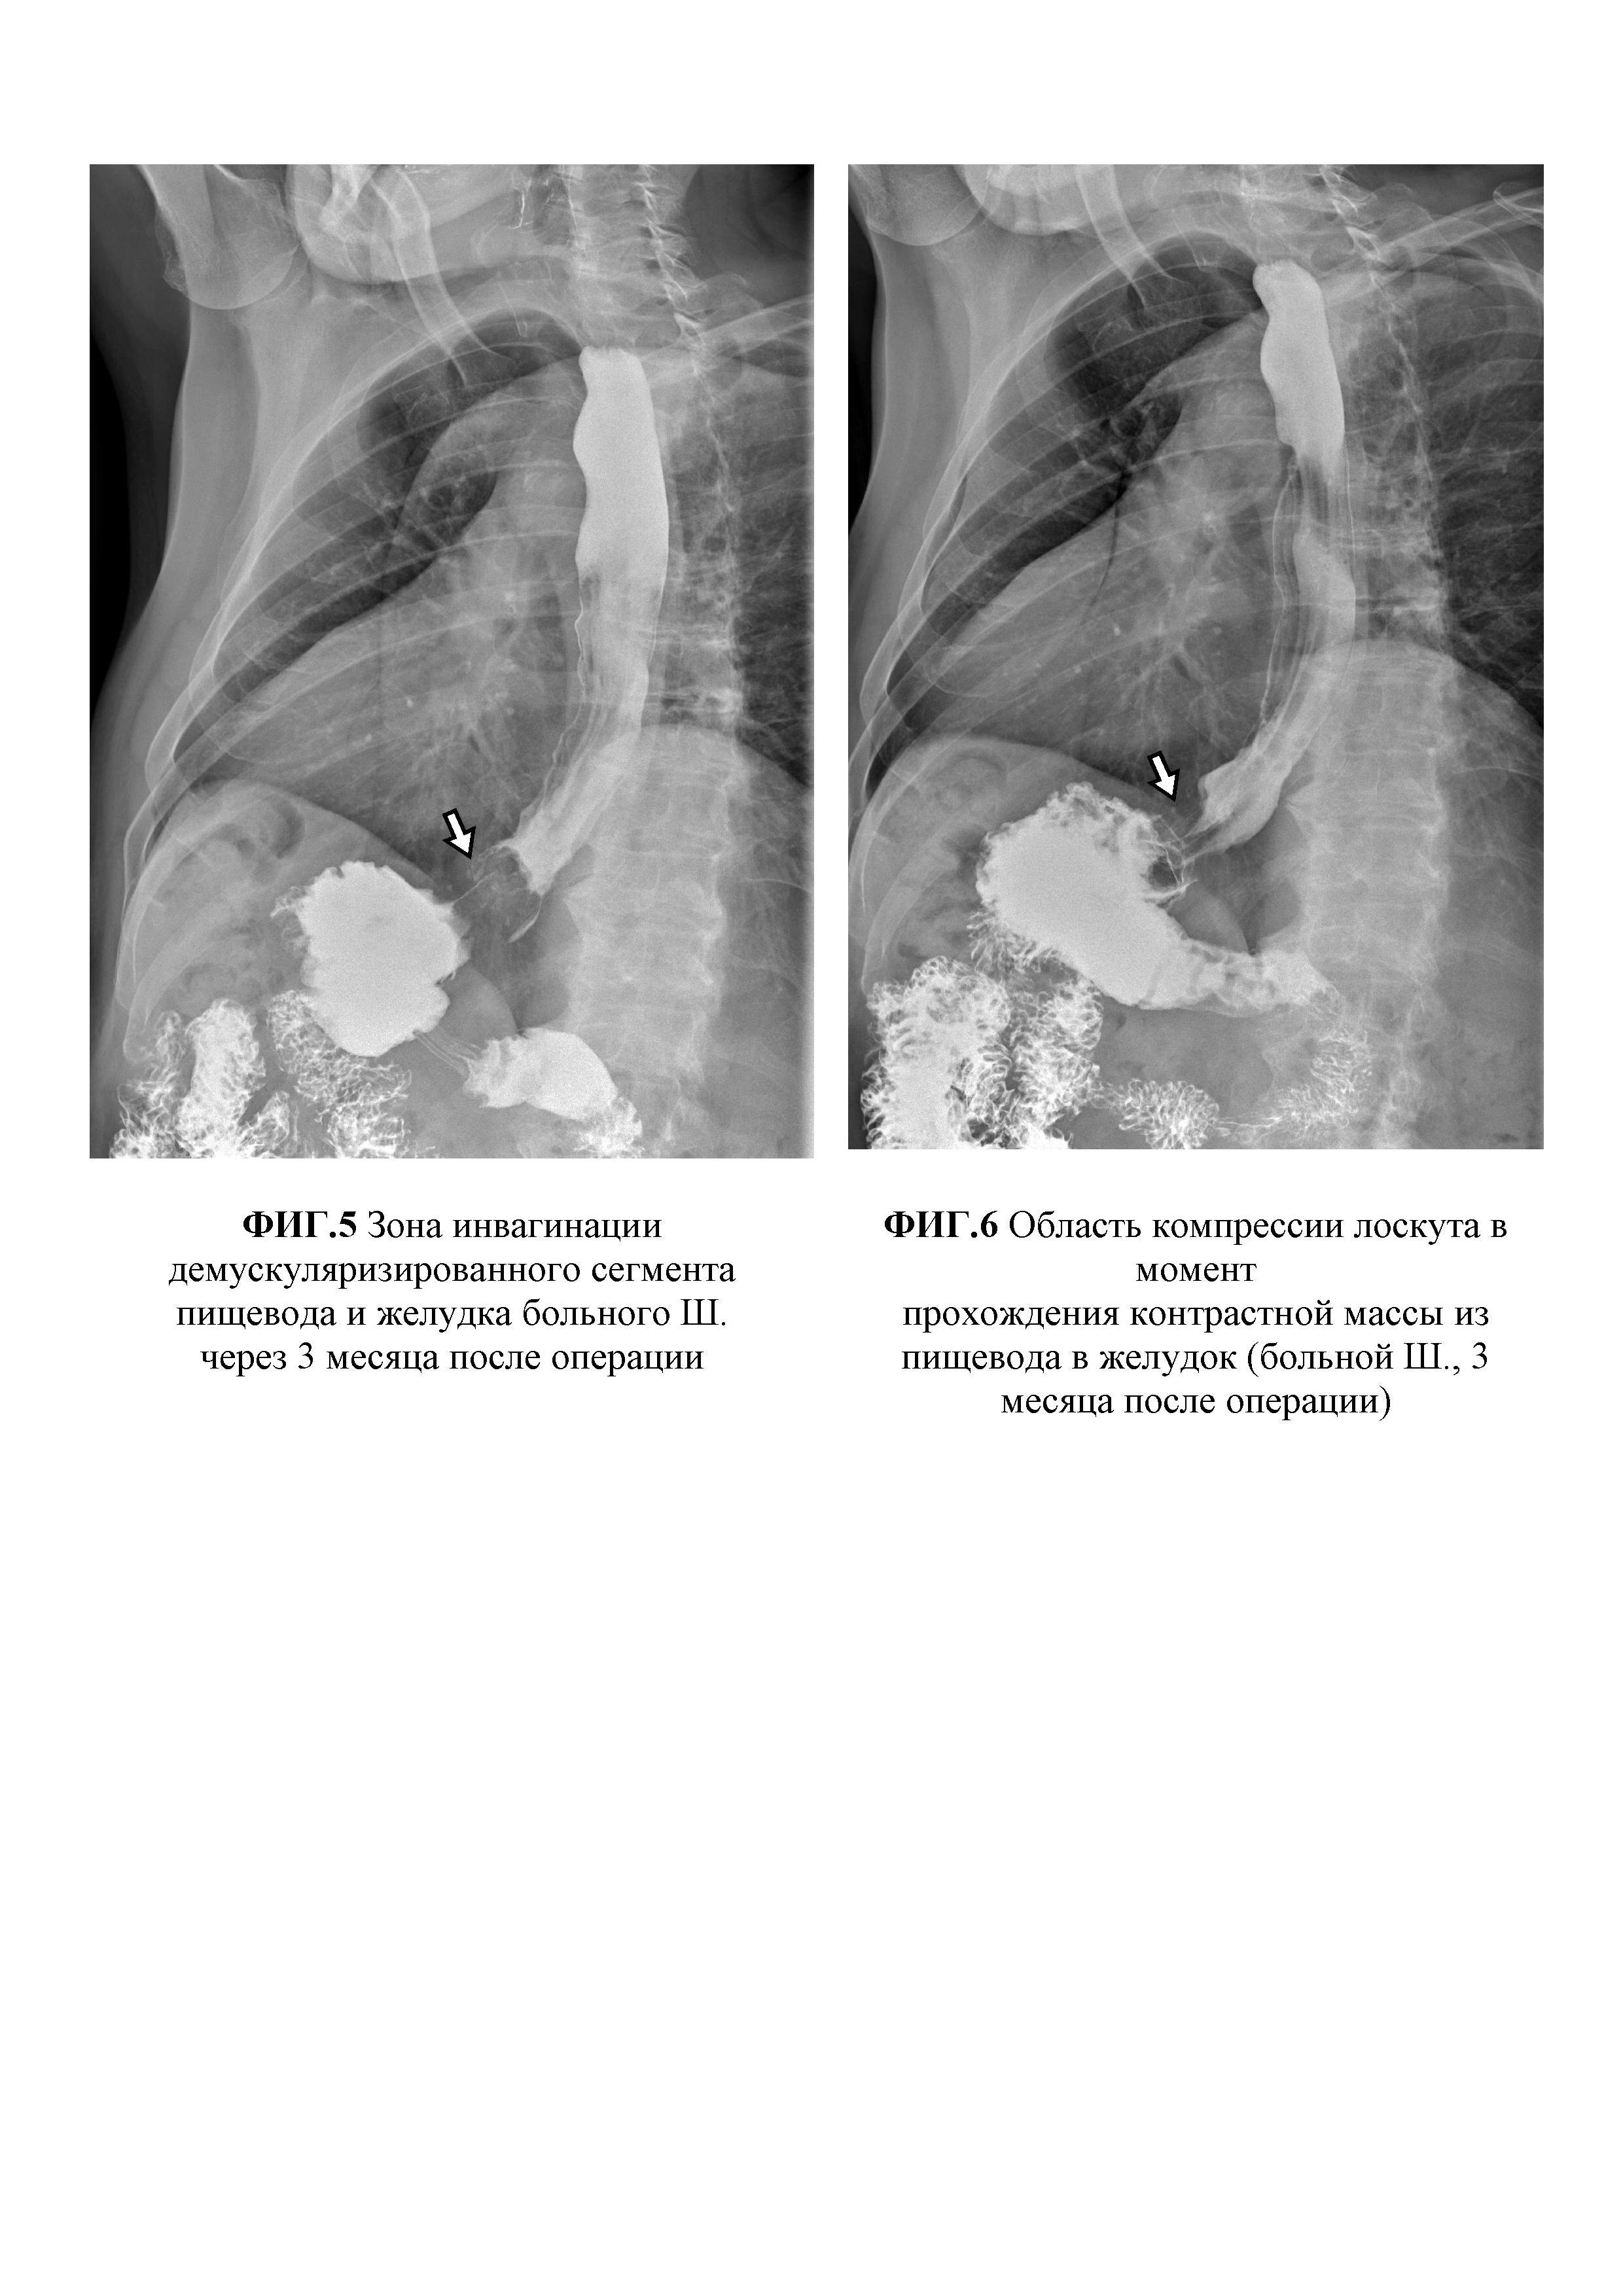

Изобретение относится к области медицины, а именно к хирургии и может быть использовано в оперативном лечении ахалазии кардии III-IV стадии с S-, L-образной деформацией пищевода. Известно много способов хирургического лечения тяжелых форм ахалазии кардии с декомпенсацией моторно-эвакуаторной функции и изменением анатомии пищевода, начиная от малоинвазивных вмешательств, например, операции Геллера, до сверх радикальных - демукозации или экстирпации пищевода. Опыт показывает, что операция Геллера низкоэффективна из-за частых рецидивов заболевания. Экстирпация и демукозация пищевода, не смотря на свою радикальность, сопряжены с опасными гнойными осложнениями, которые зачастую могут стать причиной смерти больного в раннем послеоперационном периоде. Наиболее близким по техническому решению к заявляемому способу является способ хирургического лечения ахалазии кардии III-IV стадии (патент №224217 от 25.02.2003 «Способ хирургического лечения ахалазии кардии III-IV стадии»; авторы: Кошель А.П., Жерлов Г.К., Зыков Д.В., Райш Д.В., Рыжов А.И., Артеменко М.В.), включающий мобилизацию и демускуляризацию суженной кардии и на 1,5 см проксимальнее и дистальнее места сужения на пищеводе и желудке, а также инвагинацию узловыми швами демускуляризированного подслизисто-слизистого участка в виде клапана. Данный способ имеет ряд существенных недостатков. При выполнении операции не производится низведение нижнегрудного отдела пищевода, что не оказывает влияние на расширение и девиацию пищевода. Демускуляризация суженной кардии, а также прилегающих к ней полутора сантиметров на пищеводе и желудке является недостаточным для тяжелых форм ахалазии кардии, ассоциированных с выраженной мышечной гипертрофией и декомпенсацией моторно-эвакуаторной функцией. При создании клапана не происходит образование угла Гиса и не восстанавливается естественный ход мышечных волокон кардиального сфинктера. Кроме того, формируемый клапан суживает просвет за счет сшивания над ним гипертрофированного мышечного слоя пищевода с серозно-мышечной оболочкой желудка в 1,5 см от кардии, где просвет желудка недостаточно широк. Таким образом, данный способ не может быть применим для хирургического лечения тяжелых форм ахалазии кардии с декомпенсацией моторно-эвакуаторной функции ввиду высокой вероятности рецидива заболевания. Задачей, решаемой предложенным изобретением, является разработка радикального способа лечения ахалазии кардии III-IV стадии, осложненной S-, L-образной деформацией пищевода за счет устранения расширения и искривления пищевода, восстановления его формы и тонуса, а также замыкательной и арефлюксной функции пищеводно-желудочного перехода. Новый технический результат достигают способом хирургического лечения ахалазии кардии III-IV стадии, осложненной S-, L-образной деформацией пищевода заключающийся в мобилизации и демускуляризации пищеводно-желудочного перехода вокруг зоны сужения, формирования инвагинационного клапана путем погружения демускуляризированного слизисто-подслизитого слоя узловыми швами, отличающийся тем, что путем тракции за турникет производят пристеночную мобилизацию и низведение нижнегрудного отдела пищевода до состояния его умеренного натяжения; циркулярно рассекают серозно-мышечную оболочку передней и задней стенок желудка в 3,5 см от кардии; от края разреза производят удаление серозно-мышечной оболочки желудка и низведенного пищевода в виде "чулка" на протяжении 16 см; демускуляризированный участок слизисто-подслизистого слоя инвагинируют в просвет желудка с помощью 6-ти узловых швов, наложенных по линии соприкосновения мышечных оболочек пищевода и желудка; на передней стенке желудка на 14 мм ниже швов выкраивают несвободный серозно-мышечный лоскут длиной 45 мм, шириной 20 мм с осевым типом кровообращения в области дна желудка; подслизистую площадку после выкраивания лоскута ушивают; серозно-мышечный лоскут проводят между левой стенкой пищевода и дном желудка на заднюю стенку с фиксацией лоскута на передней стенке желудка ниже его основания в фазе умеренного натяжения. Новым в изобретении является то, что путем тракции за турникет производят пристеночную мобилизацию и низведение нижнегрудного отдела пищевода до состояния его умеренного натяжения; циркулярно рассекают серозно-мышечную оболочку передней и задней стенок желудка в 3,5 см от кардии; от края разреза производят удаление серозно-мышечной оболочки желудка и низведенного пищевода в виде "чулка" на протяжении 16 см; демускуляризированный участок слизисто-подслизистого слоя инвагинируют в просвет желудка с помощью 6-ти узловых швов, наложенных по линии соприкосновения мышечных оболочек пищевода и желудка; на передней стенке желудка на 14 мм ниже швов выкраивают несвободный серозно-мышечный лоскут длиной 45 мм, шириной 20 мм с осевым типом кровообращения в области дна желудка; подслизистую площадку после выкраивания лоскута ушивают; серозно-мышечный лоскут проводят между левой стенкой пищевода и дном желудка на заднюю стенку с фиксацией лоскута на передней стенке желудка ниже его основания в фазе умеренного натяжения. Разработанный способ позволяет восстановить анатомическую форму и тонус пищевода за счет ликвидации мешкообразного расширения и петлеобразования внутригрудной части пищевода. Вследствие демускуляризации и сокращения серозно-мышечного слоя по краю резекции создается протяженный участок оголенной подслизистой основы: 10 см на пищеводе и 6 см - на желудке. Механизмы восстановления тонуса атоничного пищевода связаны с натяжением и выпрямлением внутригрудной части пищевода в процессе его низведения и инвагинации демускуляризированного подслизисто-слизистого слоя на всем его протяжении (не менее 16 см) в просвет желудка. Положительный эффект и профилактика рецидива заболевания достигается обширной демускуляризацией низведенного сегмента пищевода и верхней трети желудка, а также широким соустьем мышечных оболочек пищевода и верхней трети тела желудка. Фактически гипертрофированная мышечная оболочка пищевода растягивается с помощью 6 узловых швов при адаптации ее по краю серозно-мышечной оболочки верхней трети желудка, диаметр которой на данном участке не менее 7 см. Создание клапана из слизисто-подслизистого слоя, который вследствие ретракции тканей сокращается до 3,5 см, в сочетании с компрессией серозно-мышечным лоскутом в области левой, задней и правой стенок пищеводно-желудочного перехода обеспечивает восстановление замыкательной и арефлюксной функции. Клинический пример Больной Ш., 62 лет находился на лечении в клинике общей хирургии ФГБОУВО СибГМУ с диагнозом основного заболевания: ахалазия кардии III ст., стадия субкомпенсации, S-образный пищевод. Сопутствующая патология: ишемическая болезнь сердца, стенокардия напряжения (ФК2), постинфарктный кардиосклероз (2004 г.); хроническая сердечная недостаточность IIA; гипертоническая болезнь III ст., риск 4; хроническая обструктивная болезнь легких, стадия ремиссии. Госпитализирован в плановом порядке для оперативного лечения с жалобами на дисфагию в виде затруднения прохождения пищевого комка, сопровождающееся дискомфортом, иногда болью за грудиной, отрыжкой, неприятным запахом изо рта, снижением массы тела. Из анамнеза известно, что считает себя больным более 5 лет, когда стал отмечать затруднение прохождения пищи после глотания. Для облегчения проглатывания пищевого комка запивал небольшим количеством воды. Иногда вызывал рвоту при задержки пищевого комка, сопровождающегося чувством переполнения или распирающей болью за грудиной. Заболевание развивалось медленно, пациент состоял под наблюдением у гастроэнтеролога поликлиники по месту жительства, периодически проходил обследование и амбулаторное лечение. За последние 2,5 года похудел на 40 кг (до заболевания масса тела 105 кг; в настоящее время весит 65 кг). В связи с прогрессированием заболевания пациент направлен в клинику общей хирургии для оперативного лечения. Данные инструментальных исследований. Рентгеноскопия пищевода и желудка от 22.01.2018 г. При осмотре грудной клетки обращает внимание расширение срединной тени вправо, виден воздух и уровень жидкости в пищеводе, что подтверждается при приеме первого глотка контрастной взвеси. Акт глотания не нарушен. Пищевод имеет S-образную форму, значительно расширен на всем протяжении - натощак 30-35 мм, при исследовании с контрастом - 50-60 мм, заполнен остатками пищи и слизью, заканчивается конусовидным сужением. Кардия сужена примерно до 7-9 мм, первый глоток пропускает через 6 минут от начала исследования, затем длительный спазм и следующий глоток проходит через 9-10 мин. При отсроченном исследовании через 2 часа и 4 часа в пищеводе сохраняется 2/3-1/2 контраста. Сократительная функция пищевода резко нарушена. Складки рельефа не удается увидеть даже через 3,5 часа. В начале исследования газовый пузырь желудка вообще не виден. Сохраняется стойкое сужение на уровне кардии, максимально определяемая ширина 13 мм, здесь видны продольные складки, контуры пищевода ровные, плавные, но на уровне субкардии и малой кривизны неотчетливо контрастированы фрагменты стенки с подрытыми, неровными контурами. В желудке видны фрагменты контрастной взвеси в виде хлопьев в содержимом желудка, контуры стенок, рельеф не определяются. Желудок маленьких размеров, через 4 часа видны следы контраста в двенадцатиперстную кишку. Судить о размерах и состоянии желудка, двенадцатиперстной кишки не представляется возможным. Через 24 часа в пищеводе контрастной взвеси нет, но при этом сохраняется его выраженное расширение и наличие воздуха и жидкости натощак. Вся контрастная взвесь распределена по толстой кишке до сигмовидной. Заключение: Ахалазия кардии III ст., стадия субкомпенсации. Эзофагит, супрастенотическое расширение пищевода с S-образной деформацией (фиг. 1). Эзофагогастродуоденоскопия с эндосонографией пищевода (OLYMPUS EVISEXERA - III, Olympus EU-ME 1, OLYMPUSGIFH-180, Olympus UM-DP20-25R) от 25.04.2018 г. Осмотр с использованием узкого спектра (NBI). Вход в пищевод свободен. В просвете остатки пищи. Пищевод верхней трети расширен до 4-4,5 см, проходим до нижней трети, где просвет щелевидный за счет стойкого спазма. С небольшим форсированием удается пройти к кардии. Слизистая белесовато-розовая с участками гиперкератоза. Зона переходного эпителия четкая, ровная, расположена в 40 см от резцов. На момент осмотра хиатальное отверстие диафрагмы смыкается полностью, соответствует зоне переходного эпителия. Желудок расправился воздухом, стенки эластичные, в просвете небольшое количество прозрачной жидкости. Перистальтика прослеживается равномерно во всех отделах, в антральном отделе круговыми волнами. Слизистая желудка розовая, блестящая, ямочный рисунок четкий, желудочные поля не расширены, складки правильные, расправляются свободно. При ретрофлексии слизистая кардии полностью обхватывает тубус гастроскопа. Угол не деформирован. В препилорической части антрального отдела на малой кривизне эрозия на возвышенном основании 9×10 мм, с углубленным участком в центре, с гематином (биопсия 1 фр.+1 ст.). Подобная эрозия на большой кривизне. Привратник сомкнут, проходим свободно. Луковица двенадцатиперстной кишки достаточного объема, на верхней стенке бруннерома 6×7 мм, на нижней стенке бруннерома 6×7мм с фибрином в центре. Слизистая луковицы двенадцатиперстной кишки гиперемирована, с острыми эрозиями 2-3 мм, покрытыми фибрином (биопсия 2 фр.+2 ст.). Слизистая подковы розовая, бархатистая, рельеф соответствует тонкокишечному. На момент осмотра в просвете двенадцатиперстной кишки желчь. Перистальтика ослаблена. Большой дуоденальный сосок в типичном месте, не изменен. В заключение проведена эндосонография пищевода. Тубус эндоскопа введен в пищевод, просвет заполнен водой, проведено сканирование стенок датчиком с частотой 20 МГц. В верхней трети стенка равномерно пятислойная с толщиной 3,2 мм, четкой дифференцировкой на слои. В нижней трети слои также дифференцируются отчетливо, но отмечается утолщение стенки пищевода до 8,2 мм, за счет гипертрофии мышечного слоя до 6,6 мм. Заключение: эхо- и эндоскопические признаки ахалазии кардии III стадии. Очаговая атрофия слизистой желудка. Эрозивно-гиперпластическая гастропатия. Бруннеромы и эрозии луковицы двенадцатиперстной кишки. В плановом порядке 03.10.2018 года под общей анестезией выполнена лапаротомия, низведение и демускуляризация нижнегрудного и абдоминального отделов пищевода и верхней трети желудка с инвагинацией демускуляризированного слизисто-подслизистого слоя, формирование мышечной петли вокруг пищеводно-желудочного перехода. Верхнесрединная лапаротомия. Установлен ранорасширитель Сигала. Лигатором ARC 350 BOWA Tissue Seal PLUS произведена пристеночная мобилизация кардии и субкардии желудка, абдоминального и диафрагмального сегментов пищевода. При осмотре, начиная от кардии желудка с переходом на абдоминальный отдел пищевода, определяется ригидный участок сужения длиной 27 мм, переходящий в расширенную до 42 мм пищеводную трубку с утолщенной стенкой. На уровне пищеводно-желудочного перехода проведен турникет-держалка. Путем подтягивания за турникет продолжена мобилизация и низведение нижнегрудного отдела пищевода до состояния его умеренного натяжения. Циркулярно рассечена серозно-мышечная оболочка на передней и задней стенках желудка в 3,5 см от кардии. С помощью ножниц и электроножа выполнено прецизионное удаление в виде "чулка" серозно-мышечной оболочки верхней трети желудка и гипертрофированного мышечного слоя низведенного пищевода на протяжении 16 см (фиг. 2). Демускуляризированный участок слизисто-подслизистого слоя инвагинирован в просвет желудка путем поочередного наложения и завязывания 6-ти узловых швов по линии соприкосновения мышечных оболочек пищевода и желудка. На передней стенке желудка на 14 мм ниже швов выкроен несвободный серозно-мышечный лоскут длиной 45 мм, шириной 20 мм с осевым типом кровообращения в области дна желудка. Подслизистая площадка ушита. Серозно-мышечный лоскут проведен между левой стенкой пищевода и дном желудка на заднюю стенку и зафиксирован узловыми швами на передней стенке желудка ниже его основания в фазе умеренного натяжения (фиг. 3). К области пищеводного отверстия диафрагмы установлен трубчатый дренаж через прокол в правой подреберной области. Послойное ушивание операционной раны. В послеоперационном периоде заживление первичным натяжением. С первых суток пациент питается жидкой пищей, со вторых суток назначена щадящая диета. Моторно-эвакуаторных нарушений не отмечено. Пациент выписан 08.10.2018 г. в удовлетворительном состоянии под наблюдение хирурга и гастроэнтеролога поликлиники по месту жительства. Обследован через 3 месяца после операции. Диету не соблюдает, дисфагии нет. По данным рентгеноскопии от 28.01.2019 г. отмечено восстановление формы и тонуса пищевода, а также замыкательной и арефлюксной функции пищеводно-желудочного перехода (фиг. 4). Мешкообразного расширения пищевода и S-образной деформации не отмечено. В области пищеводно-желудочного соустья виден инвагинационный клапан высотой 3 см (фиг. 5). Между левой стенкой пищевода и дном желудка определяется край мышечного лоскута в виде постоянной зоны эластической компрессии меняющейся по ширине от 8-9 мм до 11-12 мм в процессе прохождения порций контрастного вещества (фиг. 6). В положении Тренделенбурга лежа на спине гастроэзофагеального рефлюкса не обнаружено, пассаж бария в желудок не нарушен, происходит порционно. Таким образом, разработанный способ хирургического лечения ахалазии кардии III-IV стадии с S-, L-образной деформацией пищевода является эффективным и безопасным методом лечения тяжелых форм заболевания, позволяет восстановить форму и тонус пищевода, а также замыкательную и арефлюксную функции пищеводно-желудочного перехода, при этом избежать осложнений и сократить сроки лечения больных за счет новых оперативно-технических приемов. Приложение Фигура 1. Ахалазия кардии III ст., S-образный пищевод больного Ш. Фигура 2. Демускуляризация низведенного пищевода и желудка больного Ш. Фигура 3. Завершенный вид операции больного Ш. Фигура 4. Восстановление формы и тонуса пищевода больного Ш. через 3 месяца после операции Фигура 5. Зона инвагинации демускуляризированного сегмента пищевода и желудка больного Ш. через 3 месяца после операции Фигура 6. Область компрессии лоскута в момент прохождения контрастной массы из пищевода в желудок